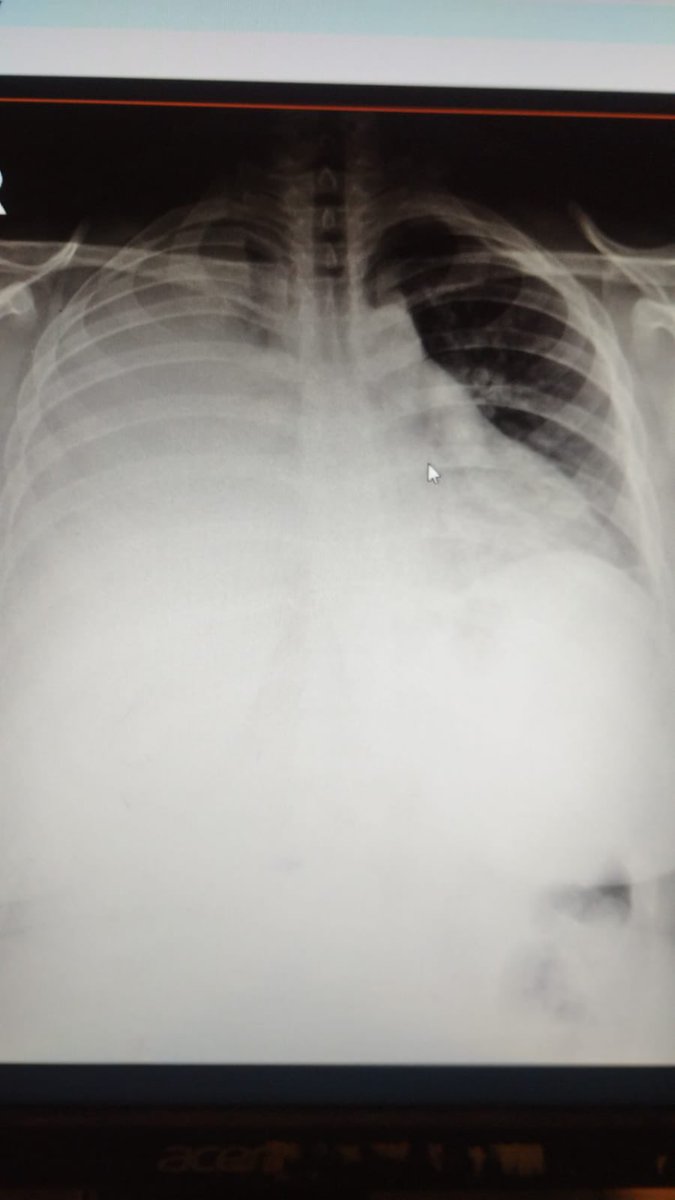

@yhybt339 @liiliisnn لا هاد pleural effusion او انصباب جنب حاد ممكن يكون سببو malign

@liiliisnn صورة الرئتين مفترض يكون لونها اسود لانو فيهن هوا بس هي المريضة عندها الرئة اليمين ( على يسار الصورة ) وقسم من الرئة اليسار متجمع فيهن سوائل لهيك صاير لونها ابيض